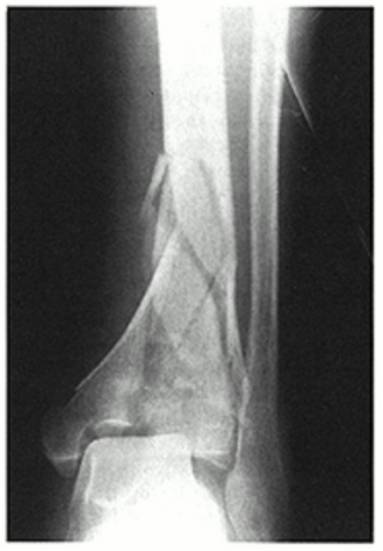

Maisonneuve骨折

由外旋暴力导致的腓骨近端骨折, 常常合并下胫腓分离、内踝骨折、三角韧带撕裂、前距腓韧带断裂、骨间韧带损伤、下胫腓韧带撕裂、后踝骨折等损伤,属于旋前-外旋三度损伤,踝关节不稳定。